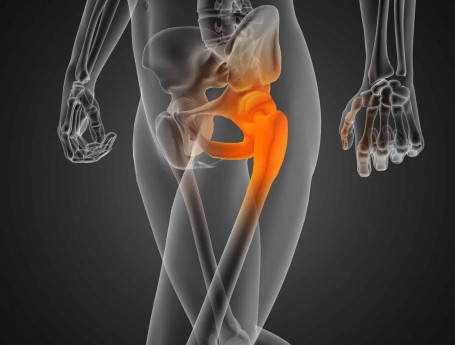

Bilateral Total Hip Arthroplasty Anterior Approach

Total Hip Arthroplasty Anterior Approach

Hip